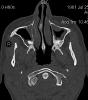

JFC Sinusitis maxilar. Espolón septal.

JFC Sinusitis Maxilar